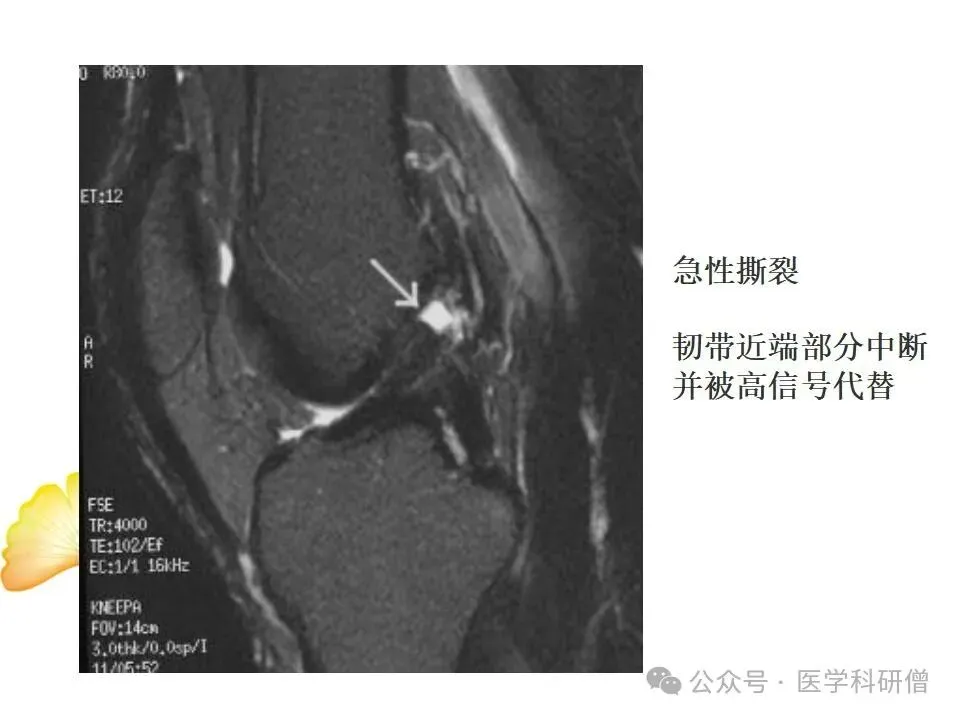

• T2加权像:对于显示水分和炎症特别敏感,能够显示韧带周围的水肿和炎症情况,对于诊断韧带损伤非常有帮助。